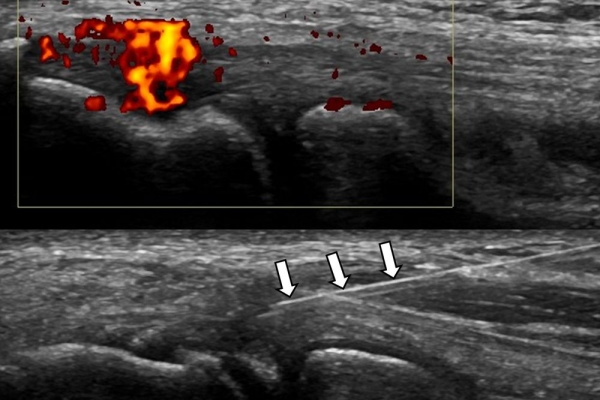

Η έγχυση γίνεται πάντοτε με την βοήθεια υπερηχογραφικού ελέγχου ώστε να είμαστε απόλυτα σίγουροι για το σημείο έγχυσης τοπικά.